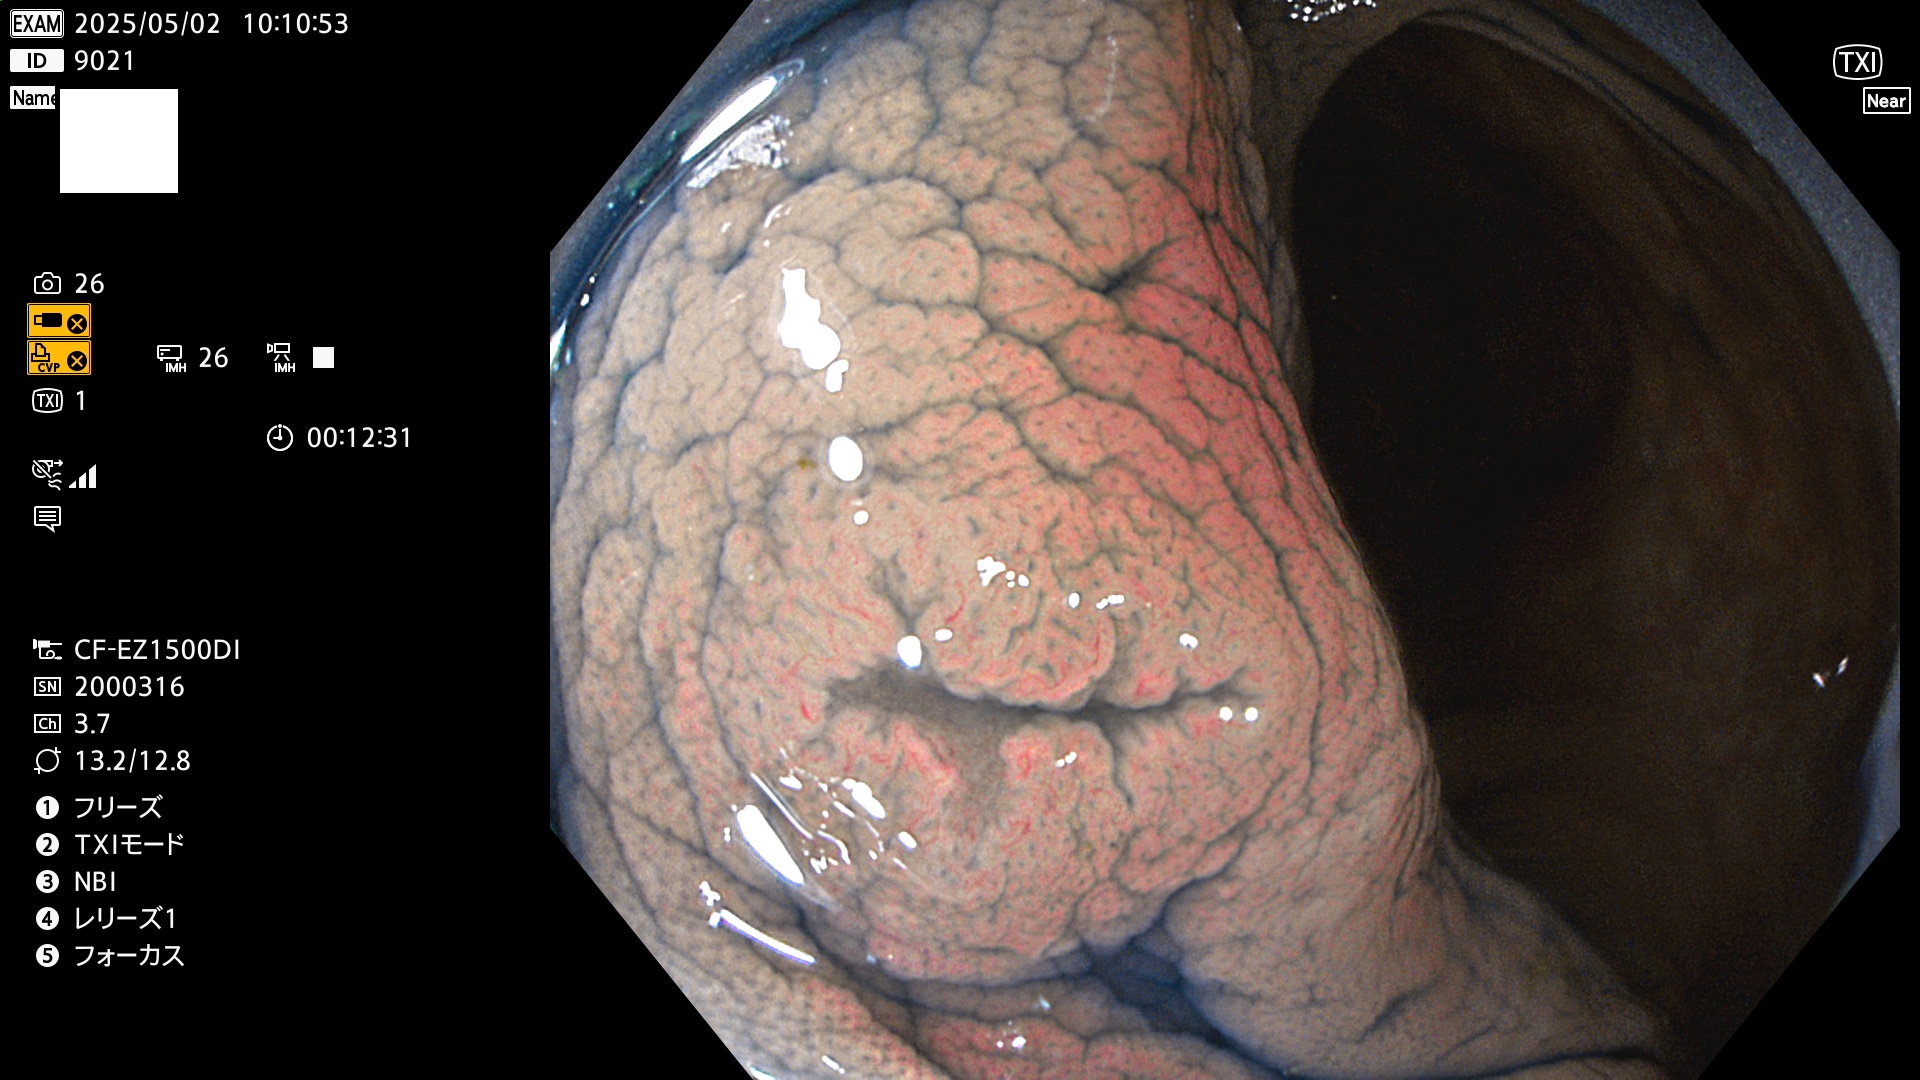

完全に平坦な物をUb、陥凹している物をUcと呼びます。Ubは認識が困難で、Ucはびらん(炎症)と紛らわしいために見落とされやすく、「内視鏡後・大腸癌」の原因になります。

抽出の対象期間 2025年5月1日〜5月2日の2日間(23件の検査)4個 (4/23=17%)